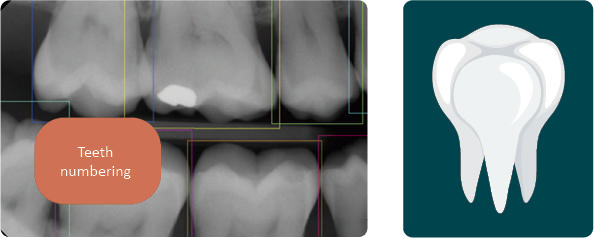

Tandsegmentering

• Identificerer og adskiller hver enkelt tand

• Understøtter struktureret dokumentation

• Kommer i foråret 2026